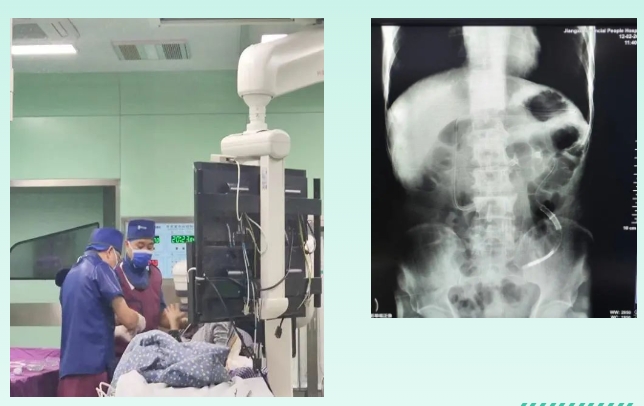

病例介绍

患者男性,75岁,因“腹痛腹胀伴肛门停止排气排便5天”于2024年2月9日转入江西省人民医院。既往有行直肠癌根治术手术史,且患有多种疾病如慢性支气管炎并肺气肿、肺部感染、心房颤动及心力衰竭等,再次行外科手术治疗面临的手术风险极大。入院后完善相关检查后,排除禁忌症,于当日在急诊介入下行经鼻插入型肠梗阻导管置入术,并予以相应补液治疗。置管一天后患者腹痛腹胀较前明显好转,症状缓解。第二田就开始出现排气排便,并遵医嘱进食流质,未再出现腹痛腹胀。小肠造影检查患者扩张肠管已消失,已恢复正常。